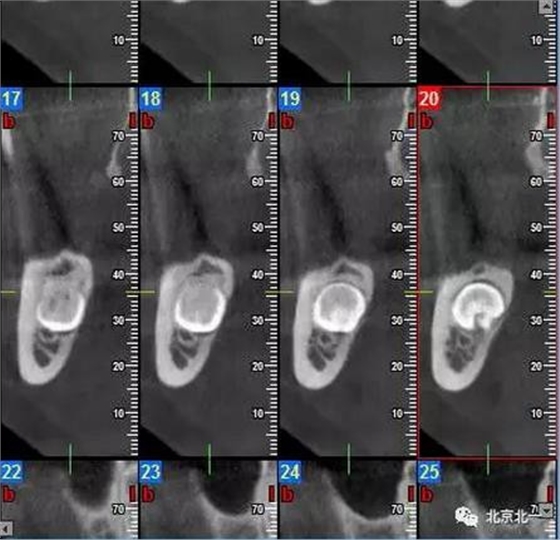

病例資料:一般情況,患者女性,28歲, 主訴:要求拔右側下頜智齒,檢查:右側下頜第三磨牙未見萌出, 拍片如圖。

圖一:CBCT顯示右側下頜水平骨埋伏牙,牙冠距離下牙槽神經管接近。

圖二:自帶的CBCT顯示下牙槽神經管貼著智齒走形。

圖三:截面圖顯示神經管位置。